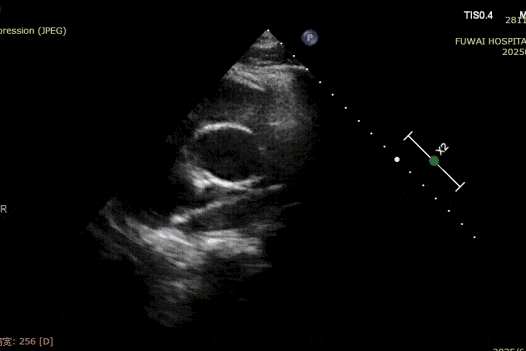

Biorąc pod uwagę bliskość ubytku do tętnicy wieńcowej, tradycyjny metalowy okluder stwarzał ryzyko kompresji, szczególnie podczas wysiłku fizycznego. Dlatego wybrano biodegradowalny okluder ASD (BDASD-I 18mm) ze względu na jego elastyczność, mniejsze ryzyko długotrwałego urazu mechanicznego oraz zdolność do degradacji do dwutlenku węgla i wody po zakończeniu funkcji zamknięcia.

Procedura była prowadzona przez TTE zgodnie z procedurą PAN opracowaną w szpitalu Fuwai. Ta bezpromieniowa technika obrazowania w czasie rzeczywistym oferuje wizualizację anatomiczną w wysokiej rozdzielczości, zapewniając dokładne umieszczenie urządzenia i minimalizując komplikacje-szczególnie cenne u młodych pacjentów w wieku rozrodczym.